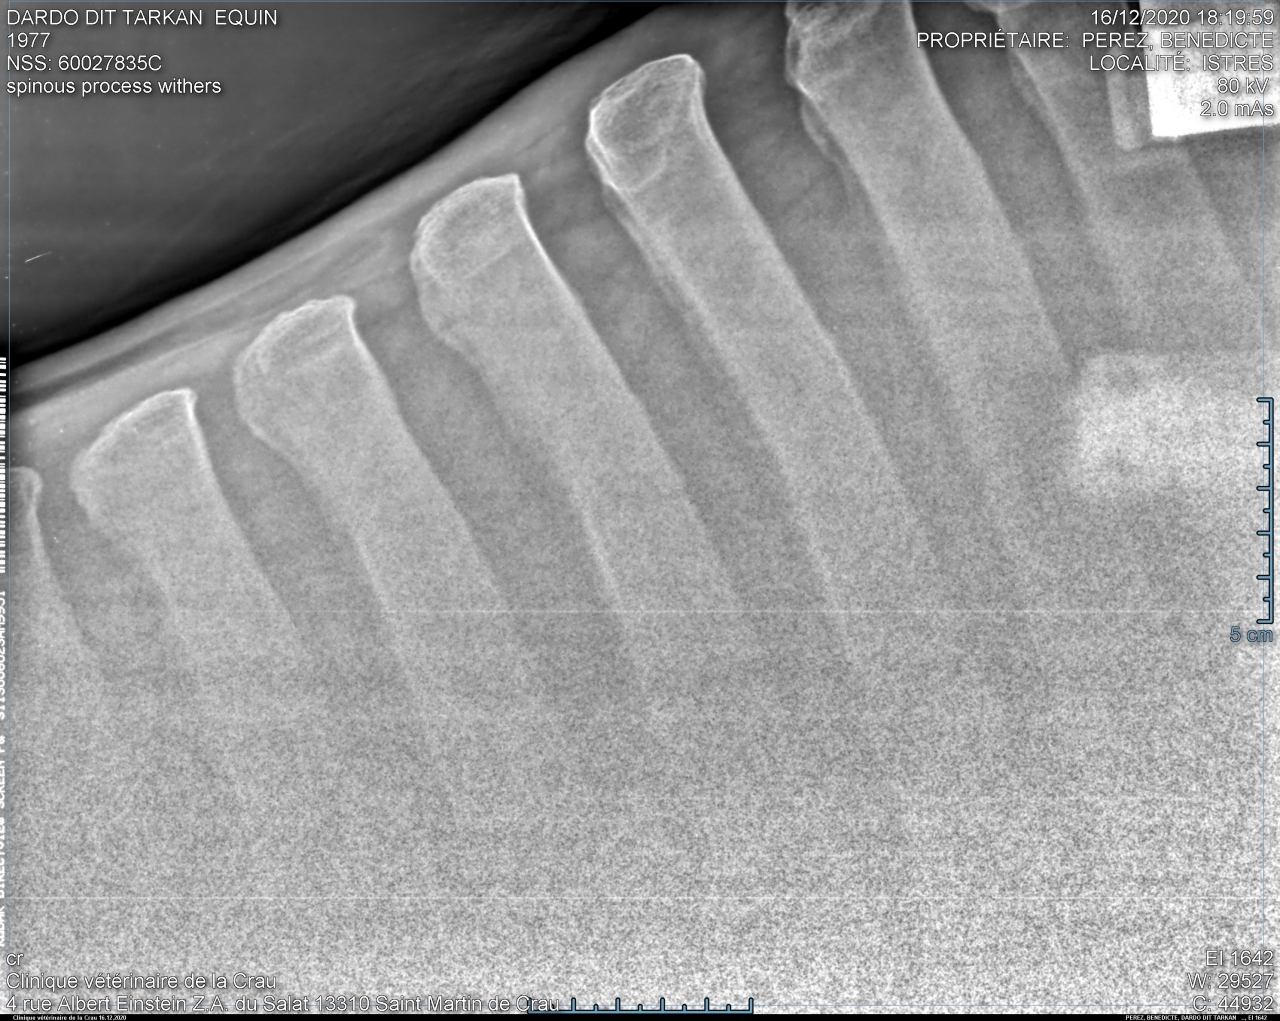

| Dire merci | bon... sans suspens aucun voilà les radios de Takhan : garrot très bien : ![]() ![]() T15/16 : la cata ![]() ![]() puis les lombaires.... acceptable mais pas génial : ![]() ![]() Je le savais mais ça fait un choc tout de meme... Je débriefe avec la véto aujourd'hui pour savoir ce qu'on fait, méso, laser? bref on va voir... Il est très très contracturé sur le dos donc déjà on va traiter ça avec mon osteo qui est aussi shiatsu girl et masseuse. Ça fait chier quand meme... |

| Dire merci | Alors oui dawa , sur les radios du garrot, tu vois que les vertèbres sont bien écartées, l'os parait visuellement "propre". Tout va bien. Sur les lombaires c'est un gros plan sur le haut des vertèbres et tu vois que l'espacement entre les vertèbres est mince mais existant. Rien ne se touche. On considère que c'est problématique quand l'espacement est en dessous de 4mm. Pour le dos, donc T15/T16 (sous mes fesses pour faire simple), tu vois que les vertèbres se touchent, et en plus, sur un coté de la radio tu vois une petite tache blanche entre les 2 vertèbres c'est ce qu'on appelle le chevauchement. Y pas encore de pont osseux donc on peut pas dire qu'il soit soudé encore.Pas complètement quoi. |